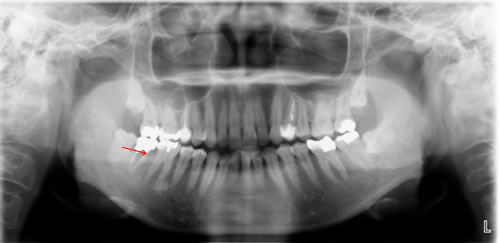

■41歳 女性 主訴 左下奥歯に食べ物がはさまる。

![]() |

|

治療前のレントゲン |